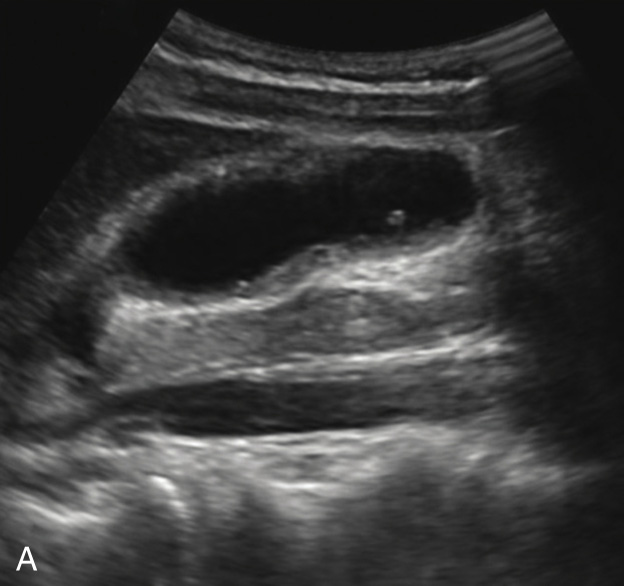

(1)局限型胆囊腺肌症:

好发于胆囊底部,灰阶超声图像通常呈边界清楚的低回声(图2-4-1A)。病变内部回声不均匀,能够观察到小片状无回声区,部分病变内可见点状高回声后伴彗星尾征(图2-4-1B)。CDFI通常无明显血流信号,部分病变内的点状高回声后方可见“快闪伪像”(图2-4-1C)。

图2-4-1 局限型胆囊腺肌症常规超声图像

A.胆囊底部低回声结节(箭头所示),边界清楚,形态规则;B.结节内可见点状高回声后伴彗星尾征(箭头所示);C.CDFI示结节内可见“快闪伪像”

GB:胆囊